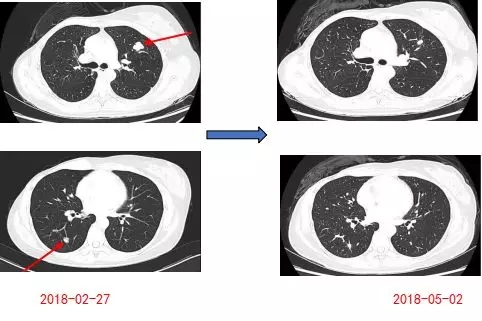

2017-04-11行“吉西他滨1000mg/m2 d1,8+阿帕替尼250mg 1/日”方案化疗6周期,疗效评估PR。

患者10周期后复查CT部分示:双肺多发转移灶,部分病灶较前增大。2018-03-01肺穿刺病理示:(左肺穿刺标本)肿瘤细胞: ER(-),PR(-),Her-2(++),AR(约30%+),结合HE切片和肿瘤病史,本例符合乳腺癌肺转移。

仔细阅片可以发现,该例患者首次复发时双肺多发转移,但在随后的在化疗中,胸部CT随访显示有的转移灶缩小,有的也出现了增大。这说明乳腺癌肺内不同部位的转移瘤存在治疗反应的差异,单个转移瘤活检,有可能不能反映所有转移瘤的生物学特性。所以,建议在治疗过程中,根据影像随访结果,在不同时间点,对治疗反应不佳的转移灶进行再次活检,有可能发现新的治疗靶点,为病人争取治疗的机会。